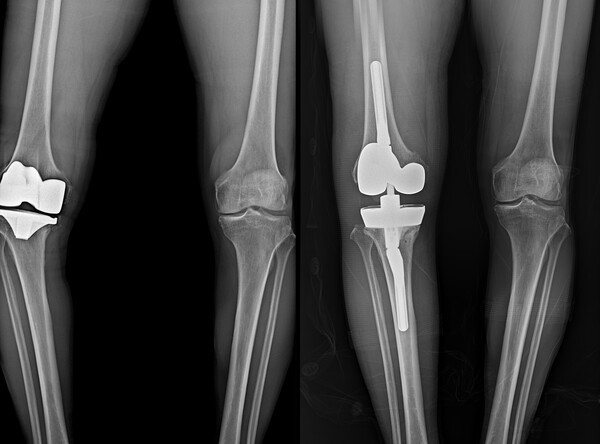

보건복지부 지정 관절전문 연세사랑병원이 무릎 인공관절 재수술 1천례를 달성했다.

연세사랑병원은 최근 10년 동안 833례의 재치환술을 시행해 국내에서 손꼽히는 재수술 경험을 보유한 의료기관으로 확인됐다.

그러나 평균 수명 증가에 따른 인공관절 마모 ▲ 부정정렬 ▲ 인공관절 불안정성 ▲ 해리 ▲ 감염 등으로 재수술이 필요한 경우가 존재한다. 국내외 연구에 따르면 전체 인공관절 수술의 약 5~10%가 재치환이 필요한 것으로 알려졌다.

재수술은 첫 수술보다 훨씬 복잡하고 고난도의 기술을 요구한다. 병원 자체 통계에 따르면 지난 10년간 재수술 환자 833명 중 58%인 483명이 70대 이상의 고령자였다. 고령 환자는 동반된 기저질환을 고려해야 하므로 수술 전 내과 전문의와의 협진이 필수적이다. 또한 재수술 원인 분석을 위한 영상의학적 진단 ▲ 감염·통증 관리를 위한 마취통증의학과 협업 ▲ 수술 후 재활 프로그램 등 다학제 시스템이 필요하다.

의료진의 임상경험과 체계적인 시스템을 바탕으로 수술 시간도 크게 단축됐다. 일반적으로 재수술은 첫 수술에 비해 두 배 이상의 시간이 소요된다. 그러나 병원 재수술센터의 평균 수술 시간은 1시간 10~20분으로 첫 수술 평균 40~50분에 비해 불과 30분 정도만 더 소요된다.